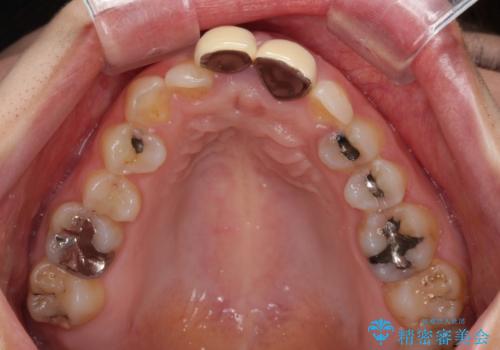

- 前歯のデコボコと、着色が著しい保険診療の前歯クラウンを気にして来院された患者様です。

左上の犬歯が埋伏しており、CT画像より萌出は困難と判断されたため、残存している歯にて歯列と咬合を整えることとしました。

前歯のクラウンは変色が顕著なため、矯正治療後にオールセラミッククラウンによる補綴治療を行うこととしました。

前歯のクラウンは、歯肉内深くに削り込まれており、歯肉の炎症が継続していたため、矯正治療後に歯周外科処置を行い、歯肉の腫れを改善させました。